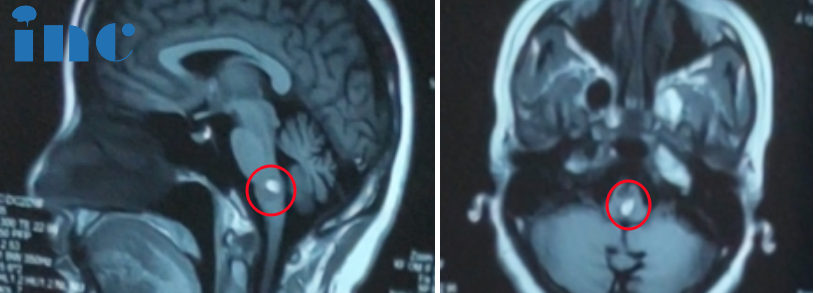

如果遇到脑干海绵状血管瘤出血

▼一开始脑干出血出院记录

2023年10月2日,

苏州大学附属独墅湖医院神经外科,

在国内手术团队的配合下,

巴教授成功为欧阳女士手术,

顺利全切脑干海绵状血管瘤。

手术结果:显微镜下全切肿瘤,手术顺利。